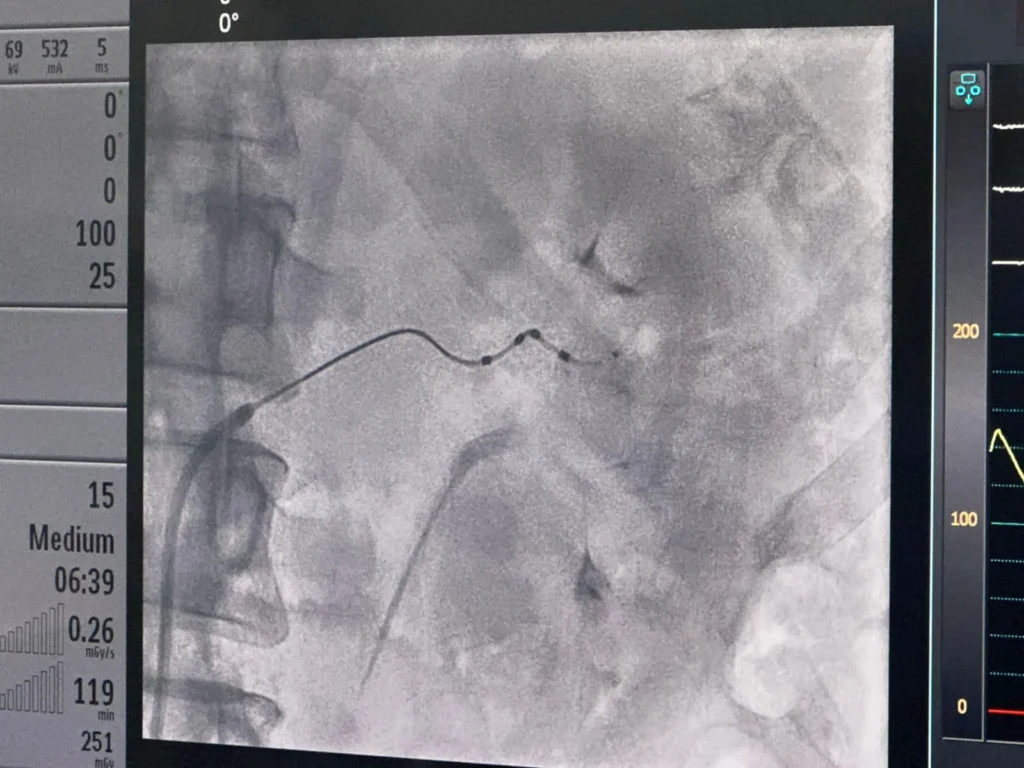

This innovative procedure targets the renal sympathetic nerves, effectively reducing their overactivity, which is a significant contributor to high blood pressure. This procedure involves inserting a catheter through right groin into the renal arteries. Where radiofrequency pulses are used to burn the sympathetic nerves. Which helps reduce high blood pressure in patients who do not respond to common medications.